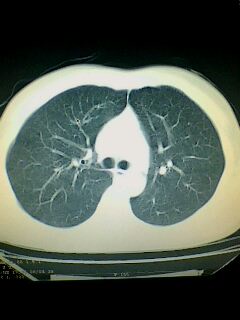

标题: CT28315:咳嗽咳痰咯血半月并胸痛 [打印本页]

标题: CT28315:咳嗽咳痰咯血半月并胸痛

1、纵膈窗效果不好,初步考虑左肺下叶感染性病灶,建议正规抗炎治疗后复查   2、右肺下叶陈旧性病灶伴局部胸膜增厚。

左下肺肿块影,深分叶,考虑肺癌。

不排除左肺下叶周围型肺癌可能!建议穿刺活检!

考虑左肺下叶周围型肺癌。

考虑左肺下叶周围型肺癌并阻塞性肺炎。